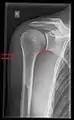

X-ray

Projectional radiography views of the shoulder include:

Transaxillary projection

The arm should be abducted 80 to 100 degrees. This method reveals:[24]

• The horizontal alignment of the humerus head in respect to the socket and the lateral clavicle in respect to the acromion

• Lesions of the anterior and posterior socket border, or of the tuberculum minus

• The eventual non-closure of the acromial apophysis

• The coraco-humeral interval